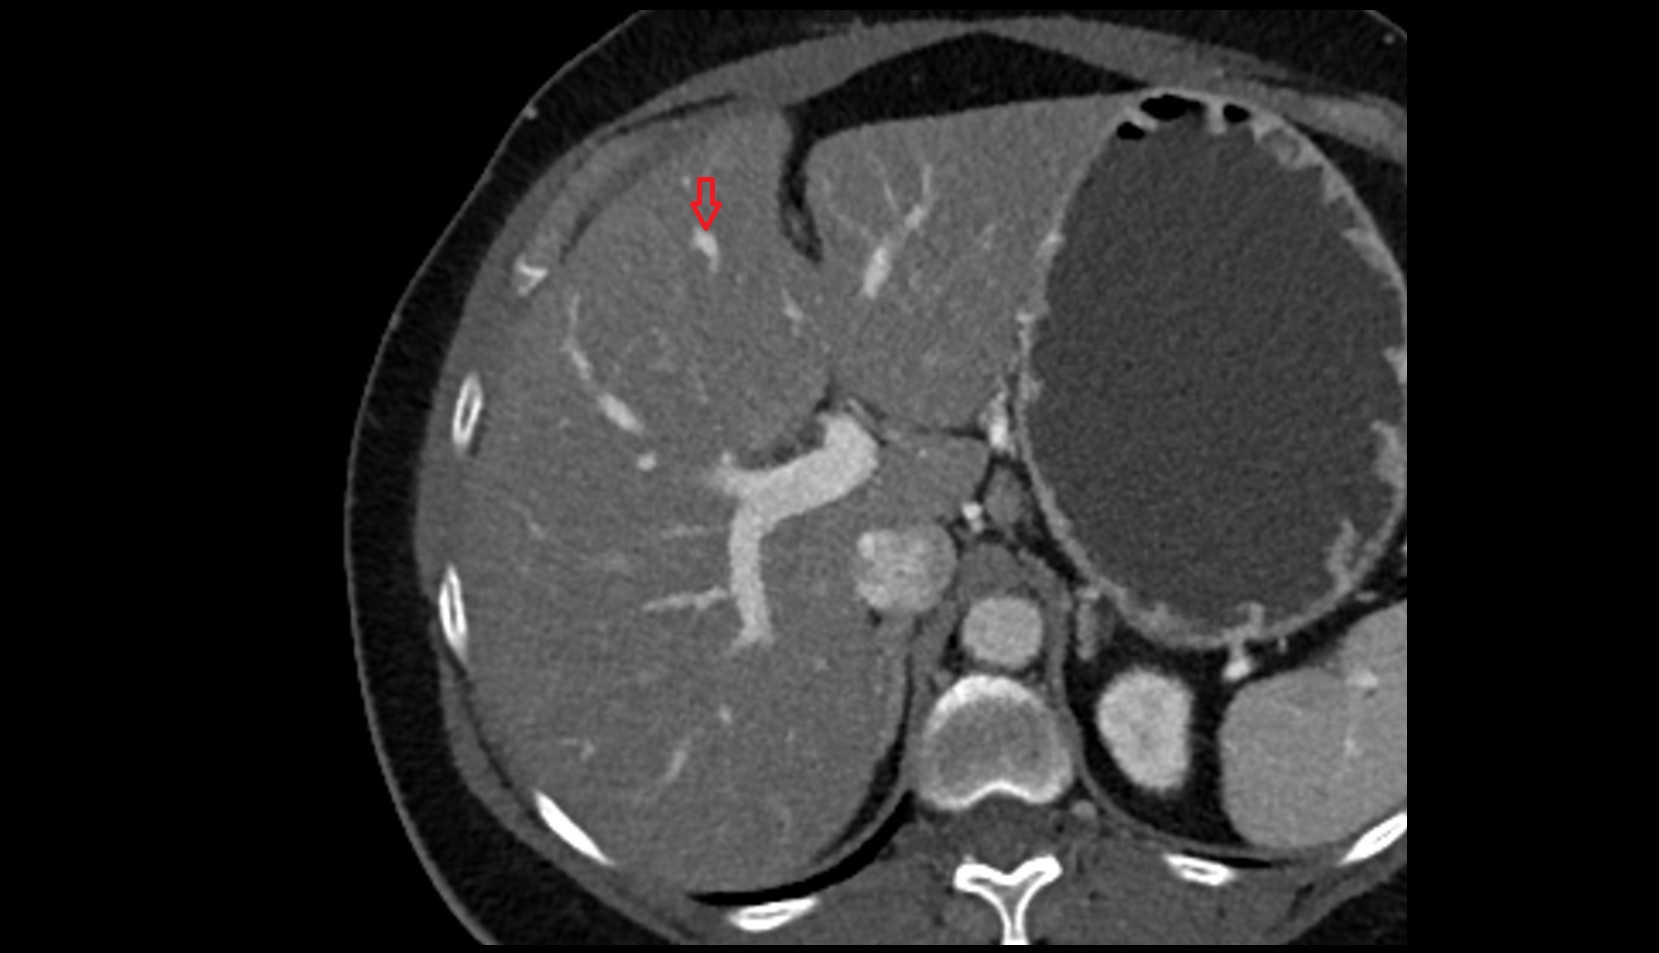

- Liver

- Left lobe of liver

- Right lobe of liver